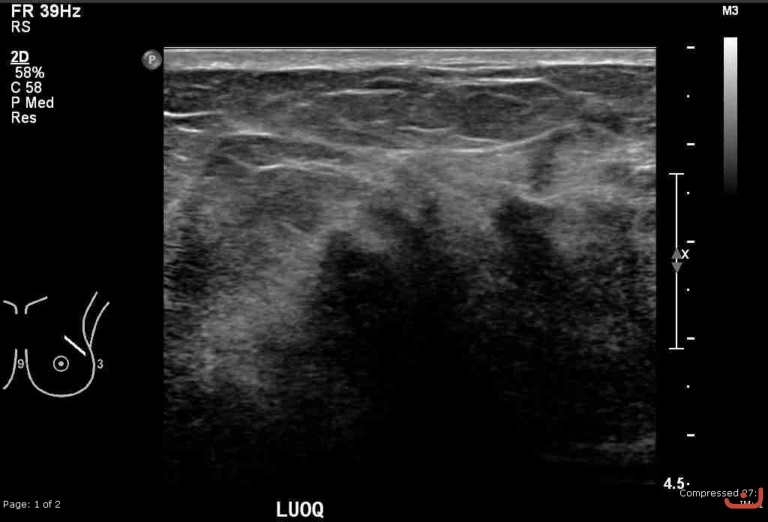

Malignant solid mass

Date

Thursday, 30 April 2015

File size of the original image

149.43 KB (768 x 522 px)